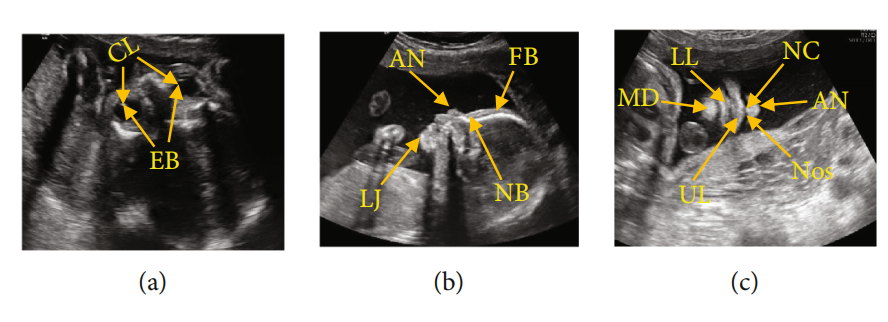

图1:FFUSP(a)OAP图像,其中CL代表晶状体,EB代表眼球;(b) MSP,FB代表额骨,NB代表鼻骨,AN代表鼻尖,LJ代表下颌骨;(c)NCP,AN代表鼻尖,NC代表鼻柱,Nos代表鼻孔,UL代表上唇,LL代表下唇,MD代表下颌骨

FFUSP由三个基本平面组成(图1):眼轴向平面(OAP)、中位矢状面(MSP)和鼻唇冠状面(NCP)。